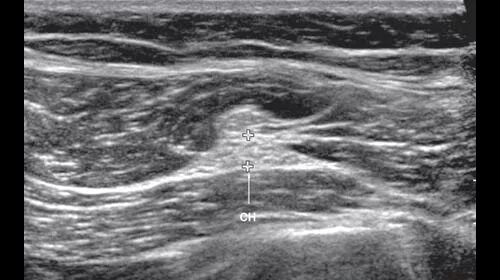

Узи нервов сделать в москве